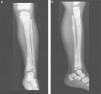

Presentation of the CaseA 4-year old male with a history of blindness in relation to congenital optic neuropathy of non-filiation aetiology and delayed growth. He presented at the emergency department after low intensity trauma in the right leg. An X-ray was taken which showed a fracture in the distal shaft of the tibia and fibula, together with a fracture callus in the proximal third of the fibula and general sclerosis of the visible bony structures which indicated sclerosing bone dysplasia (Fig. 1). The radiologic study was completed with a bone series, where a diffuse increase in bone density was highlighted with a “bone within bone” appearance and the enlargement of long bone metaphysis (Figs. 2–4). Radiologic findings determined the diagnosis of osteopetrosis.

X-rays of the right leg in anteroposterior (a) and lateral (b) projection. Transversal fracture in distal shaft of the right tibia and fibula. Fracture callus in proximal end of fibula. General sclerosis of the visible bony structures with poor differentiation between cortical and medullary cavity.